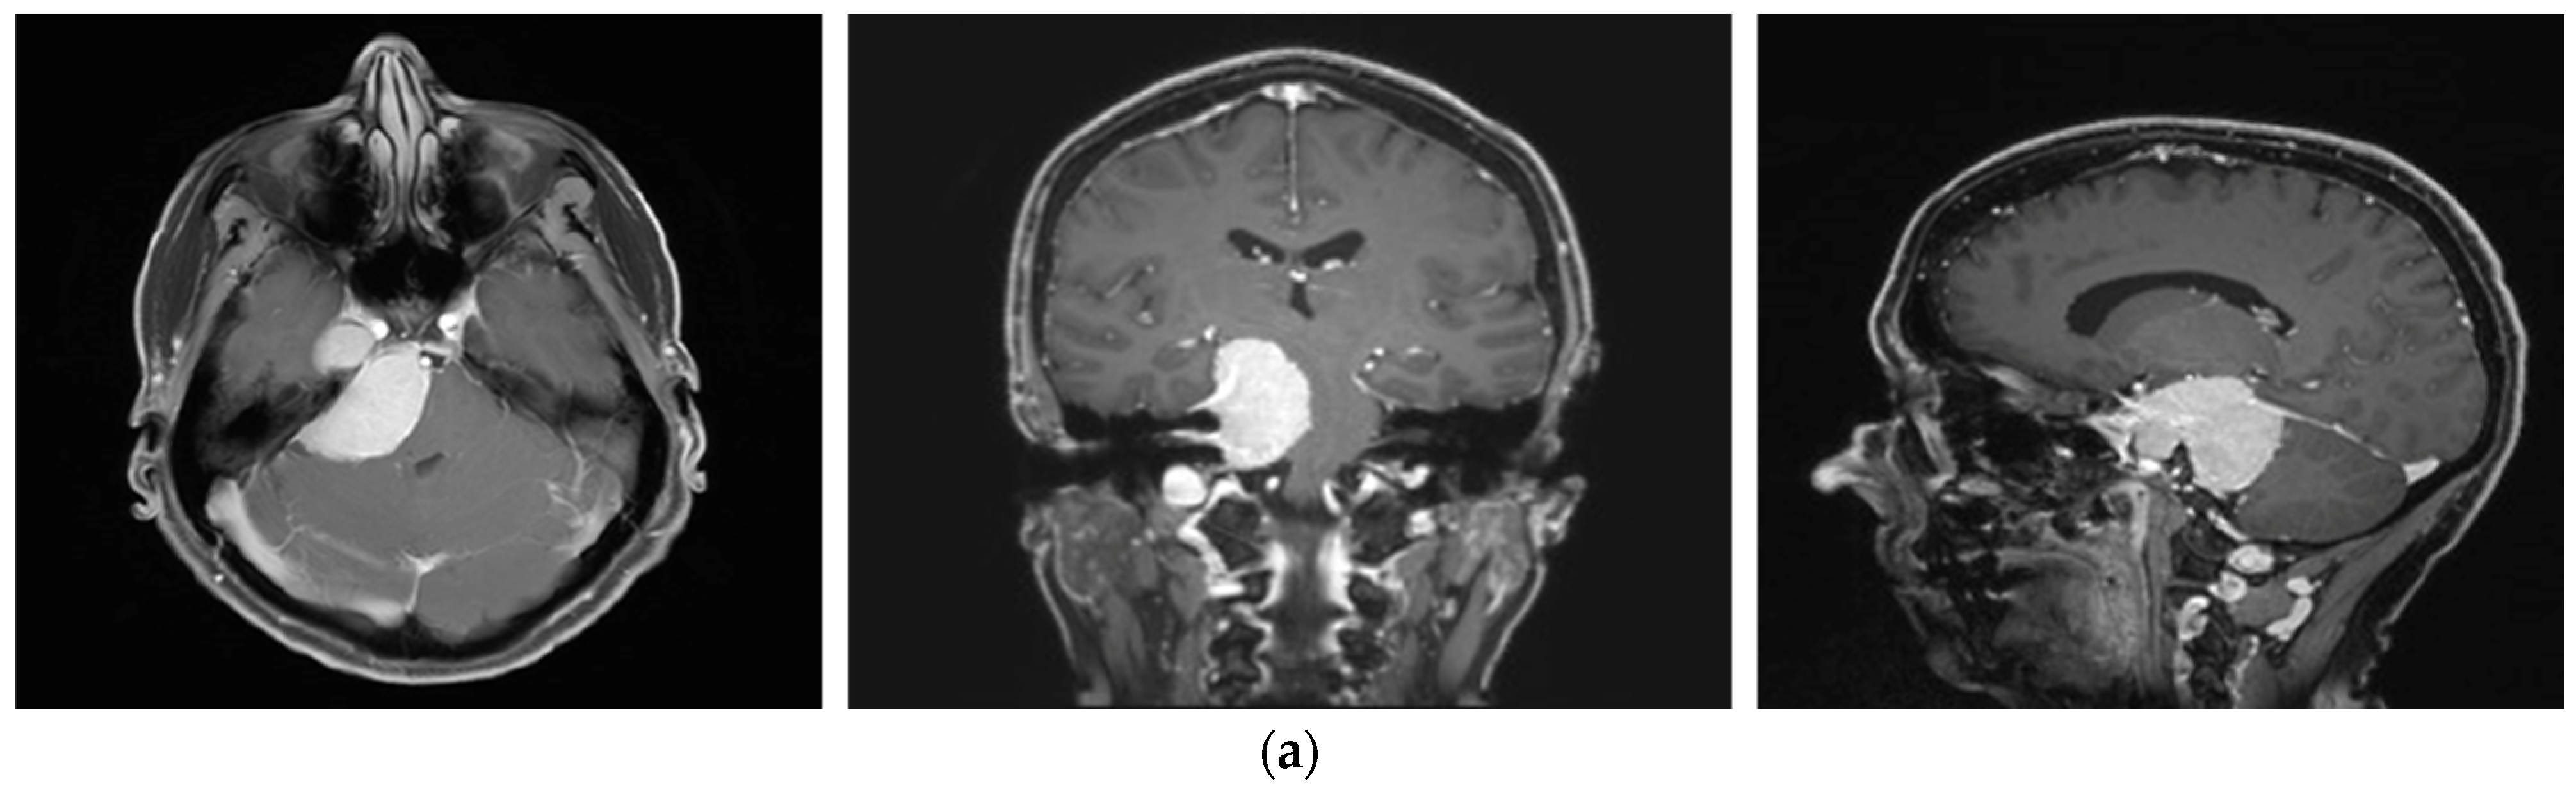

A 58-year-old female presented with progressive headache, difficulty swallowing, diplopia, hearing loss, and reduced face sensitivity on the right side (Figure 4). Elective craniotomy and AHSA-assisted tumor resection were performed. The patient underwent hypofractionated radiosurgery (5 × 5 Gy) of the residual meningioma one year after tumor resection.

Figure 4.

Second representative case of AHSA-supported tumor resection. (a) MRI imaging of petroclival meningioma (axial, coronal, sagittal). (b) Depiction of preoperative tumor volume (orange) and planned residual tumor volume (red). (c) AHSA summary table showing the stereotactic radiation constraints for the preoperatively planned residual tumor volume. With this plan, conventional fractionation and hypofractionation were feasible with effective tumor coverage.

—brainstem: mean dose is safe, while the max. dose is marginally safe;

—right optic tract: mean dose unsafe, max. dose is marginally safe;

—right hippocampus: marginally safe, and mean dose unsafe, max. dose is marginally safe. (d) First intraoperative structure update (ISU) with a residual tumor volume of 82% with the calculated dose constraints for conventional and hypofractionated radiotherapy. Single dose stereotactic radiosurgery was not feasible with this degree of remaining tumor. At this point, the dose constraints for conventional radiotherapy were:

—brainstem: mean dose is safe, max. dose is marginally safe;

—right hippocampus: mean dose unsafe, max. dose is marginally safe. Hypofractionated radiotherapy:

—brainstem: marginally safe;

—right cochlea: mean dose unsafe, max. dose safe;

—right hippocampus: mean dose unsafe, max. dose is marginally safe. (e) Second intraoperative ISU with residual tumor volume of 74% and calculated dose constraints for hypofractionated radiotherapy. Single dose stereotactic radiosurgery was still not considered feasible with this residual tumor volume. The dose constraints for organs at risk for conventional and hypofractionated radiotherapy were unchanged compared to the first ISU. (f) Third intraoperative ISU with residual tumor volume of 47% and calculated dose constraints for conventional, hypofractionated radiotherapy, and radiosurgery. The current dose constraints for organs at risk were the following for conventional radiation:

—right hippocampus: mean dose unsafe, max. dose is marginally safe. Hypofractionated radiation, which was unchanged for the first and second ISU:

—right hippocampus: mean dose unsafe, max. dose is marginally safe. For single fraction radiosurgery, the OAR dose constraints were available but considered to be unsafe.

—brainstem: mean dose unsafe, max. dose safe;

—chiasma: unsafe;

—right cochlea: unsafe;

—left optic tract: mean dose unsafe, max. dose safe;

—right optic tract: unsafe;

—right hippocampus: unsafe. (g) Overlay of preoperatively estimated and intraoperative effective residual tumor volume in AHSA. (h) Final intraoperative dose constraints after last ISU and data fusion with intraoperative CT. The dose constraints for OARs appeared to improve and were as follows for conventional and hypofractionated radiotherapy:

—brainstem: mean dose is safe, max. dose is marginally safe.

—brainstem: mean dose safe, max. dose unsafe;

—chiasm: mean dose unsafe, max. dose safe;

—right optic tract: mean dose unsafe, max. dose safe. (i) Comparison of pre- and 3 months postoperative MRI for stereotactic radiation planning. The residual tumor was finally treated with hypofractionated radiotherapy (5 × 5 Gy).